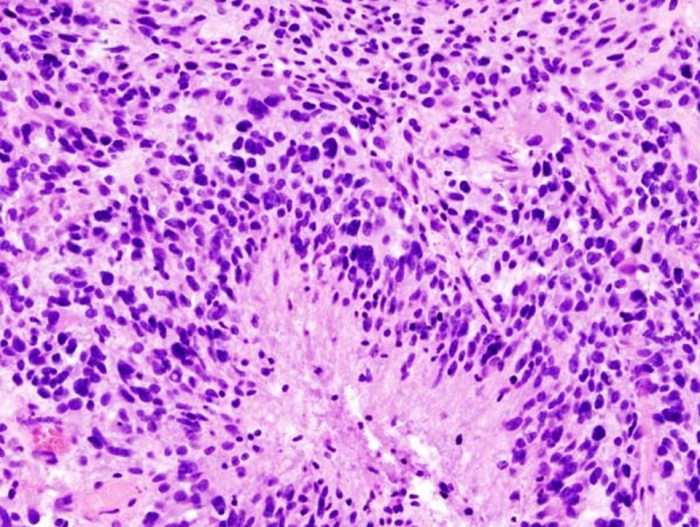

L’incidence du glioblastome multiforme (GBM), l’une des tumeurs les plus mortelles, a vu sa prévalence augmenter de plus du double en Angleterre entre 1995 et 2015 selon de nouvelles analyses des statistiques nationales. Pendant ce laps de temps, le nombre de cas de ces tumeurs est passé de 983 à 2 531.